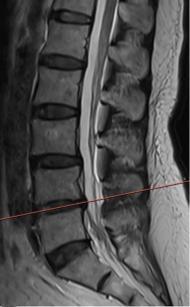

• 不同入路脊柱内镜手术治疗L4/5节段脱垂型腰椎间盘突出症的疗效比较

摘要:目的 观察经椎间孔入路内镜下腰椎间盘切除术(TELD)和经椎板间入路内镜下腰椎间盘摘除术(IELD)治疗L4/5节段脱垂型腰椎间盘突出症(LDH)的临床疗效。方法 回顾性分析2020年11月-2022年11月该院采用脊柱内镜手术治疗的75例L4/5节段脱垂型LDH患者的临床资料。根据手术入路的不同,将患者分为TELD组(53例)和IELD组(22例)。比较两组患者的手术情况和术后疗效。结果 与TELD组比较,IELD组的手术时间明显缩短,术中透视次数明显减少,差异均有统计学意义(P < 0.05);两组患者住院时间和并发症发生率比较,差异均无统计学意义(P > 0.05)。所有患者术后均获得12~19个月的随访。两组患者末次随访时的视觉模拟评分法(VAS)评分和Oswestry功能障碍指数(ODI)明显低于术前,且IELD组明显低于TELD组,差异均有统计学意义(P < 0.05)。按照突出物和神经根的不同位置进一步分析,两组肩上型患者(TELD组10例,IELD组6例)末次随访时的VAS评分和ODI明显低于术前,且IELD组末次随访时的VAS评分明显低于TELD组,差异均有统计学意义(P < 0.05);两组腋下型患者(TELD组8例,IELD组16例)末次随访时的VAS评分和ODI明显低于术前,且IELD组明显低于TELD组,差异均有统计学意义(P < 0.05);35例肩前型患者经TELD术后,末次随访时的VAS评分和ODI明显低于术前,差异有统计学意义(P < 0.05)。按照突出物的不同Lee分区进一步分析,两组Lee Ⅲ区患者(TELD组44例,IELD组10例)末次随访时的VAS评分和ODI明显低于术前,且IELD组的ODI明显低于TELD组,差异均有统计学意义(P < 0.05);两组Lee Ⅳ区患者(TELD组9例,IELD组12例)末次随访时的VAS评分和ODI明显低于术前,且IELD组明显低于TELD组,差异均有统计学意义(P < 0.05)。结论 采用TELD和IELD治疗L4/5节段脱垂型LDH,均可获得较满意的减压效果,但IELD的手术时间相对较短,X线透视次数较少,且对肩上型、腋下型、Lee Ⅲ区和Lee Ⅳ区的减压效果更有优势。